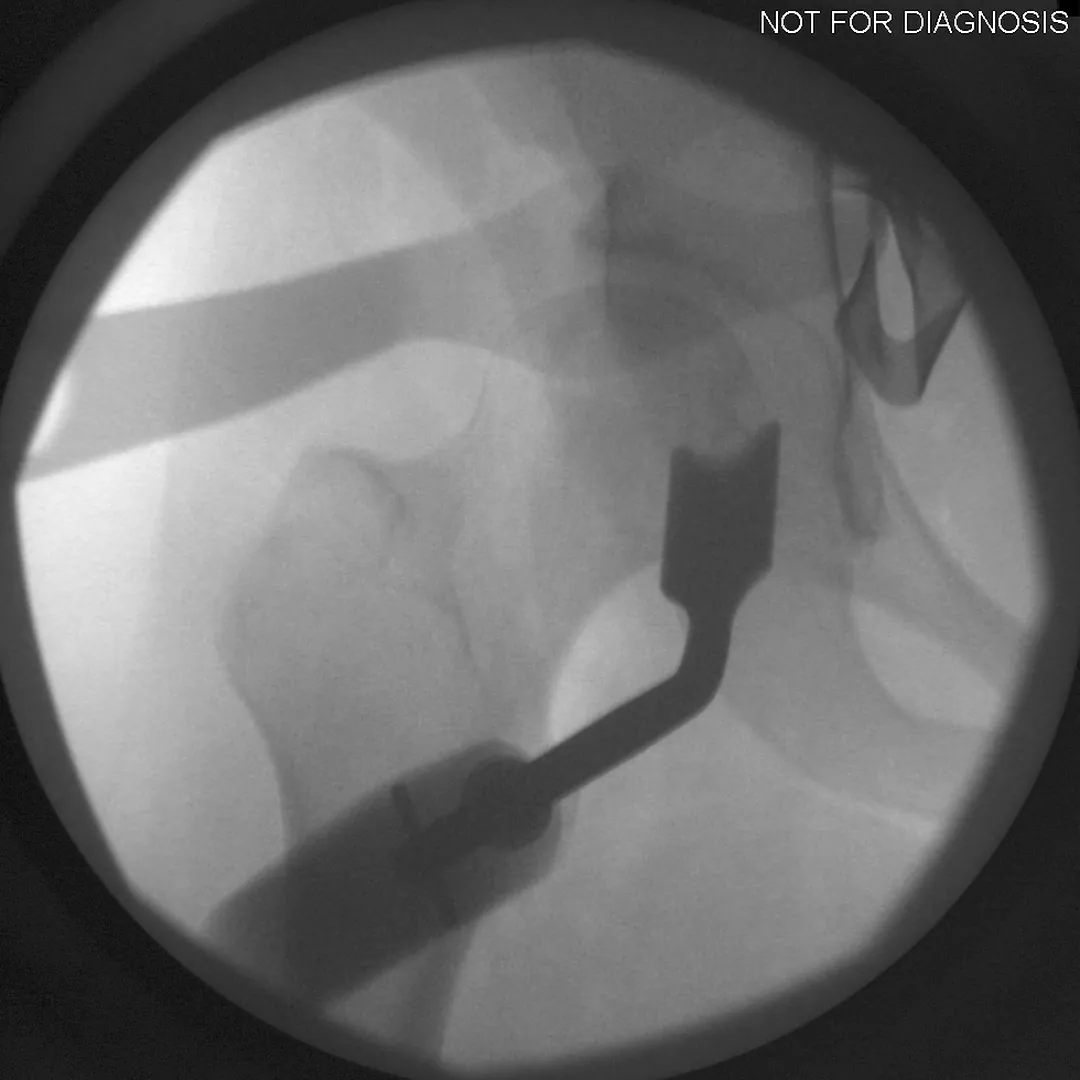

During a PAO, the surgeon carefully cuts the bone around the hip socket and repositions it to provide better coverage of the femoral head. The socket is then fixed in its new position using screws. The goal is to improve hip stability, reduce pain, and preserve the patient’s natural hip joint.

Diagram 3: Hip After Periacetabular Osteotomy (PAO)

• Acetabulum repositioned to improve femoral head coverage

• Load more evenly distributed across the joint

• Screws shown securing the acetabulum in its new position